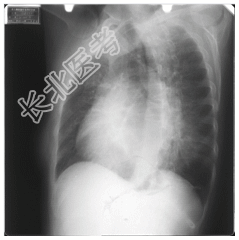

- [材料题] 女,50岁,主诉:胸闷、心悸4个月。听诊:心尖部听到舒张期和收缩期杂音。

- 简答题1、请问该案例诊断是什么?

- 简答题2、请问诊断依据是什么?